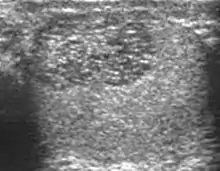

Primary leukemia of the testis is rare. However, due to the presence of blood-testis barrier, chemotherapeutic agents are unable to reach the testis, hence in boys with acute lymphoblastic leukemia, testicular involvement is reported in 5% to 10% of patients, with the majority found during clinical remission. The sonographic appearance of leukemia of the testis can be quite varied, as the tumors may be unilateral or bilateral, diffuse or focal, hypoechoic or hyperechoic. These findings are usually indistinguishable from that of the lymphoma [Fig. 9].

Fig. 9. Leukemia. Diffuse hypoechoic infiltrative lesions are seen involving the whole testis, indistinguishable from that of the lymphoma.